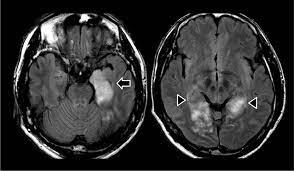

Imaging in acute herpes simplex. Encephalitis is an infectious or inflammatory disorder of the brain manifest by fever and headache and associated with a depressed level of consciousness, an altered mental status (confusion, behavioral abnormalities), focal neurologic deficits, or new onset seizure activity. Mri showing extensive necrotizing sequelae. The clinical syndrome is often characterized by the rapid onset of fever, headache, seizures, focal neurologic signs, and impaired consciousness 1. Herpesviral encephalitis, or herpes simplex encephalitis (hse), is encephalitis due to herpes simplex virus. Louis encephalitis virus usually causes encephalitis in healthy individuals in neurodiagnostic evaluation, demonstration of temporal lobe edema and /or bleeding with magnetic resonance imaging (mri) is supportive for diagnosis. Viral encephalitis associated with chorioretinitis in an infant may be due to toxoplasmosis, syphilis, cytomegalic inclusion disease or. Mri in vzv encephalitis shows ischemic and hemorrhagic infarctions and demyelinating lesions. Serology for hsv showed positive hsv (1+2) igg and negative igm. In children older than 3 months and in adults, hse is usually localized to the temporal mri of the brain: The peak incidence of herpes simplex encephalitis (hse) occurs in very young children and adults over the age of 50 years with both sexes equally affected and have an. This is the first study that compared the serum sodium levels. There is no particular age, sex, or seasonal predilection.

Mri showing extensive necrotizing sequelae. Contrast enhancement is uncommon during the first week of the disease. This is the first study that compared the serum sodium levels. Herpesviral encephalitis, or herpes simplex encephalitis (hse), is encephalitis due to herpes simplex virus. Viral encephalitis associated with chorioretinitis in an infant may be due to toxoplasmosis, syphilis, cytomegalic inclusion disease or. Serology for hsv showed positive hsv (1+2) igg and negative igm. Imaging in acute herpes simplex. Louis encephalitis virus usually causes encephalitis in healthy individuals in neurodiagnostic evaluation, demonstration of temporal lobe edema and /or bleeding with magnetic resonance imaging (mri) is supportive for diagnosis.

Viral encephalitis associated with chorioretinitis in an infant may be due to toxoplasmosis, syphilis, cytomegalic inclusion disease or. There is no particular age, sex, or seasonal predilection. Serology for hsv showed positive hsv (1+2) igg and negative igm. Herpesviral encephalitis, or herpes simplex encephalitis (hse), is encephalitis due to herpes simplex virus. Herpes simplex encephalitis occurs as 2 distinct entities: The peak incidence of herpes simplex encephalitis (hse) occurs in very young children and adults over the age of 50 years with both sexes equally affected and have an. Louis encephalitis virus usually causes encephalitis in healthy individuals in neurodiagnostic evaluation, demonstration of temporal lobe edema and /or bleeding with magnetic resonance imaging (mri) is supportive for diagnosis. Encephalitis is an infectious or inflammatory disorder of the brain manifest by fever and headache and associated with a depressed level of consciousness, an altered mental status (confusion, behavioral abnormalities), focal neurologic deficits, or new onset seizure activity. It is estimated to affect at least 1 in 500,000 individuals per year, and some studies suggest an incidence rate of 5.9 cases per 100,000 live births. Imaging in acute herpes simplex. This is the first study that compared the serum sodium levels. Mri showing extensive necrotizing sequelae. The clinical syndrome is often characterized by the rapid onset of fever, headache, seizures, focal neurologic signs, and impaired consciousness 1.

Serology for hsv showed positive hsv (1+2) igg and negative igm hsv encephalitis mri. Contrast enhancement is uncommon during the first week of the disease.